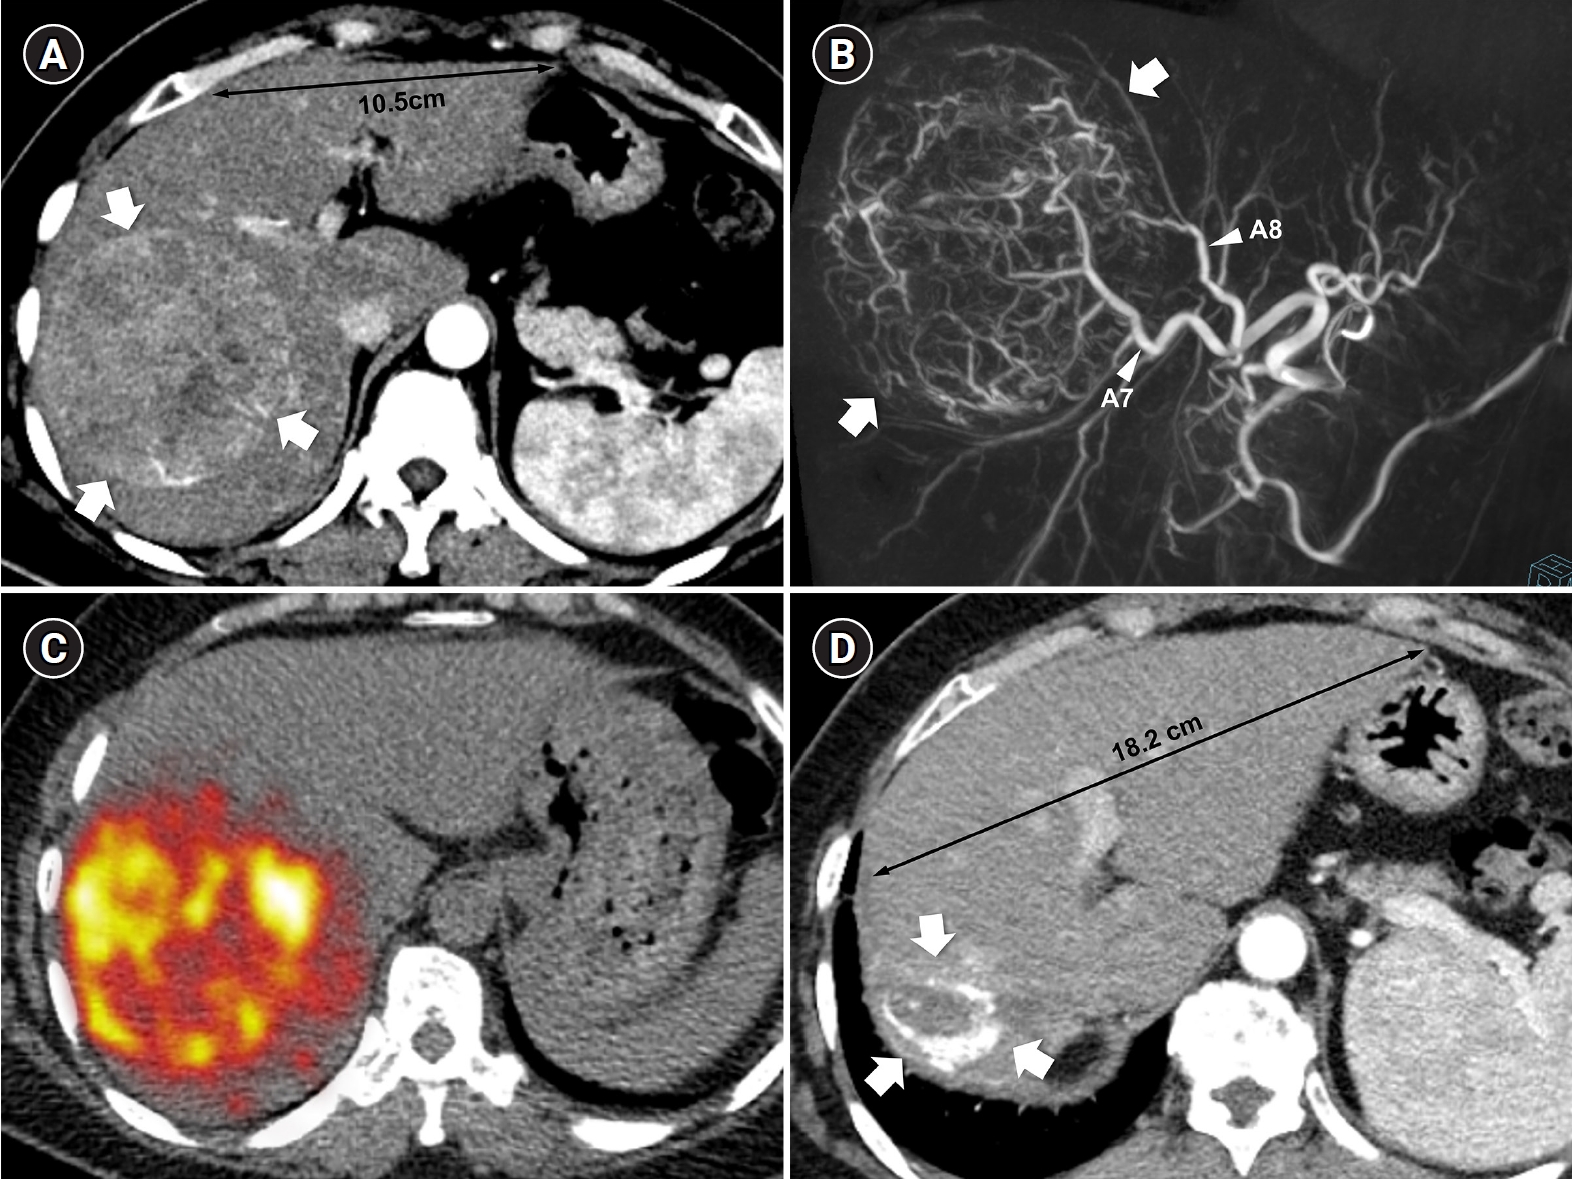

Fig. 2.

Radiation major hepatectomy in a 60-year-old woman with hepatocellular carcinoma. (A) Contrast-enhanced computed tomography (CT) shows a 9.0-cm hypervascular tumor (arrows) with two satellite nodules (not shown) in segments 7 and 8. (B) Cone-beam CT hepatic arteriography shows tumor staining (arrows) supplied by A7 and A8 (arrowheads). A total of 9.11 GBq of glass microspheres was infused via A7 and A8. (C) Post-treatment Y-90 positron emission tomography shows intense uptake throughout the tumor, consistent with complete microsphere coverage, with a perfused liver dose of 355.3 Gy and a tumor dose of 609.9 Gy. (D) Fifty-month follow-up CT shows complete response with dystrophic calcification (arrows), atrophy of segments 7 and 8, and compensatory hypertrophy of the left hepatic lobe (double arrowheads).

Recent advances in dosimetry optimization have markedly improved the therapeutic outcomes of TARE. Radiation segmentectomy and radiation lobectomy have expanded the role of TARE from a palliative treatment to a potentially curative modality. In early or localized HCC, radiation segmentectomy can achieve complete necrosis by delivering ablative radiation doses confined to one or two hepatic segments (Fig. 1). In the LEGACY study, which included patients with solitary HCCs (median diameter, 2.7 cm; range, 1.0 to 8.1 cm), radiation segmentectomy achieved a 2-year complete response (CR) rate of 84% [12]. In the RASER trial, a single-center prospective study conducted in patients with solitary HCCs ≤ 3 cm, the initial objective response rate was 100 % [18]. This outcome was superior to that reported in a Korean retrospective study (2-year CR rates in 1–10 cm HCCs: 66.2% with conventional TACE and 30.5% with drug-eluting bead TACE [DEB-TACE]) and a Japanese randomized controlled trial (3-month CR rates in 1–5 cm HCCs: 75.2% with conventional TACE and 27.6% with DEB-TACE) [19,20]. Several studies have further demonstrated that radiation segmentectomy can achieve local tumor control rates comparable to those of surgical resection or local ablation, when appropriate dosimetry is achieved [21]. Even for multifocal or bulky tumors, Korean investigators have expanded this principle beyond segmentectomy into a broader concept of radiation “major hepatectomy,” applying ablative doses to larger anatomical territories when disease remains confined and hepatic reserve is adequate (Fig. 2). A Korean study reported a median time to progression of 17.1 months in patients with tumors averaging 11.4 cm in size treated at mean absorbed doses of 418.8 Gy [22]. Radiation lobectomy can also be used when resection is technically feasible but unsafe because the future liver remnant (FLR) is insufficient [23]. By intentionally delivering sufficient radiation dose to non-tumorous parenchyma in the target lobe, contralateral hypertrophy can be induced while simultaneously suppressing tumor progression in the treated lobe [24]. Taken together, these results indicate that territory-based TARE with high radiation dose can serve as a reasonable alternative in patients who are technically resectable but medically inoperable, or in those initially considered for resection who later become unsuitable because of comorbidities or limited hepatic reserve [25].